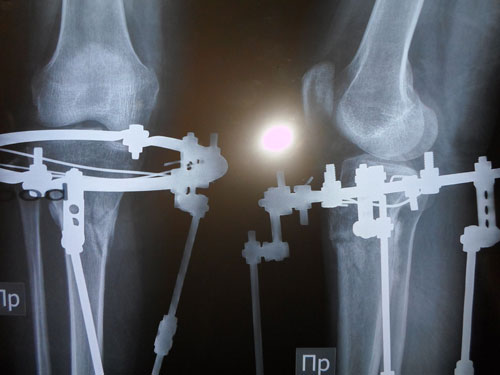

Леди, получили Ваши рентгеновские снимки. костная мозоль растёт хорошо.

108 дней со дня операции.

Рентгеновские снимки 108 дней.

Дата операции 04.10.2012г.

Срок лечения правая нога - 114 дней, левая - 117 дней.